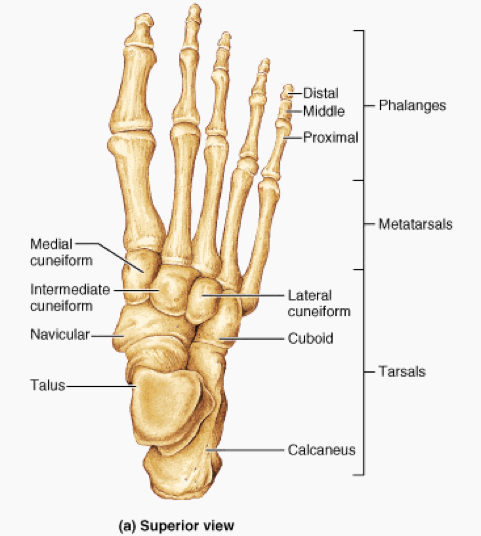

2. found in the feet as well

1. are known as tarsals